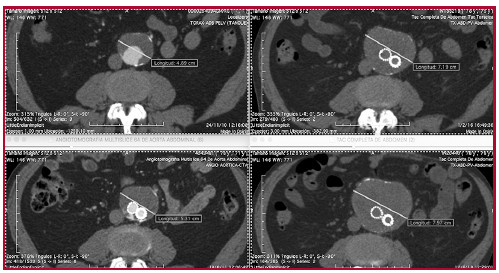

En seguimientos sucesivos se determinó la presencia de endofuga tipo II, la cual fue seguida por imágenes tomográficas hasta que alcanzó los 76 mm, momento en que se decidió su tratamiento. (Figura 1) En la imagen radiográfica se verificó, además, una pequeña migración de la rama contralateral a la altura de su inserción en el muñón contralateral.

Mediante la inyección de 100 ml de CO2 a 300 mm de Hg, a través de un introductor femoral e inyección automatizada (Angiodroid Srl., San Lazzaro, Bologna, Italia), se pudo evidenciar una endofuga tipo II a expensas de la arteria iliolumbar, rama de la arteria hipogástrica izquierda (Figuras 2a y 2b). Luego de su canulación selectiva, se evidenció un nido en el saco aneurismático, que tenía, además una rama eferente lumbar. Se decidió entonces la embolización con coils fibrados (Concerto 3D Detachable Coil System, Medtronic, Santa Rosa, EUA) de las ramas aferentes, eferentes y nido de la endofuga. Posteriormente se colocó una extensión ilíaca Cook de 13 mm de diámetro (Cook Inc., Bloomington, IN, EUA) para reparar la endofuga tipo III. (Figura 2c)

(AIL, arteria iliolumbar) alimentando la endofuga tipo II. Resultado final con la embolización con coils de la arteria aferente, eferente y nido de la endofuga con coils.